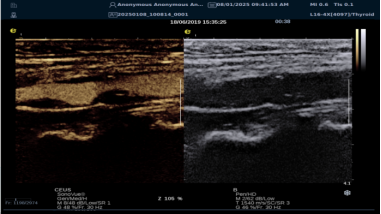

iPlane Vascular 平面波超微细血流显像技术

iPlane Vascular 技术借助 OmniSound?平面波和 3D 壁滤波技术突破,提升超声多普勒分辨率并具备定量测量能力。优势如下:

image.png

? 显著提高对低速血流的敏感度,实现高分辨率、高帧频实时微血流成像(分辨率 30 微米、帧频 150 /s),动态显示斑块内新生血管血流。

? 基于多普勒原理进行频谱测量与 VI 指数计算,定量评估斑块内新生血管。

? 成像质量接近造影效果且无需造影剂,无创简便,增强诊断准确性,适用于细微血流变化场景。